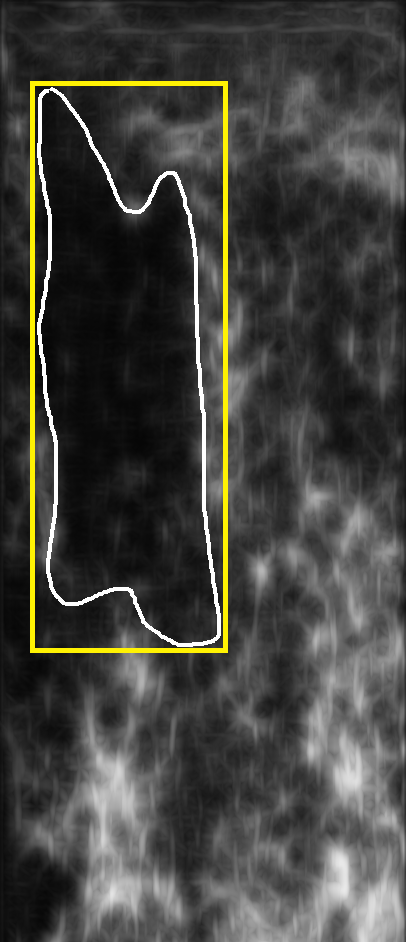

As evident from the relatively low contrast images shown in Fig. 3, any segmentation technique will have difficulty to extract the tumours as marked by the expert. This was verified by experimenting using several methods such as thresholding, active contours, and watershed segmentation. As the ultimate goal is to characterize the tumour for treatment prediction, we can aim to get an ROI segmented that roughly sketches the tumour region instead of attempting to extract the precise tumour contour. Hence, we propose to use a novel approach, namely barcode-guided ROI segmentation, which aims at finding a bounding box around the tumour instead of actual tumour contour.

where was a proper membership function, and had darkening effect on the image. To suppress the speckle noise present in ultrasound images, sticks filter [23] was used. Fig. 3 shows some sample images with their corresponding ground-truth, and preprocessed versions.

Assuming that there is a set of training images along with their ground-truth segments, we propose to use barcodes in order to estimate the location of a bounding box around the tumour (contoured by the expert as a ground-truth) with starting coordinates and ending coordinates (Fig. 4). Two barcodes were assigned to each bounding box: a global barcode for the entire image, and a local barcode for the bounding box (Fig. 5). The rough localization of a bounding box for the tumour can be formulated as a search problem: given a database consisting of training images with their corresponding bounding boxes , and global and ROI Radon barcodes , the bounding box was formulated for a query image by first finding the top similar images in the database via Hamming distance between corresponding barcodes:

Both query bounding box and the estimated bounding box were then reshaped into binary images and and compared using Dice coefficient to measure the accuracy: . Algorithm 1 provides the details of the proposed method.

4 Leave-One-Out Validation